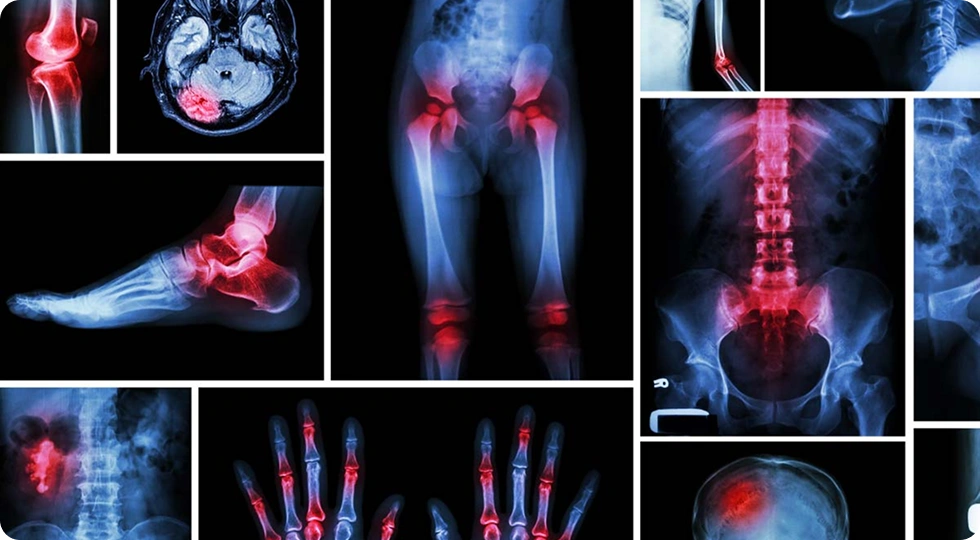

The Department of Orthopaedics provides comprehensive care for bone, joint, and musculoskeletal conditions. With advanced facilities such as C-arm imaging, arthroscopy, and modern operation theatres, the department manages trauma, fractures, joint replacements, and deformity corrections with precision. Our experienced faculty offer excellent clinical training and academic guidance to students through case discussions, workshops, and hands-on learning. The department is dedicated to promoting patient care, research, and professional excellence in orthopaedic education.